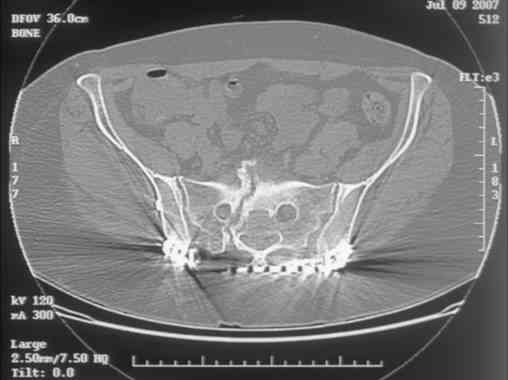

Here is a magnified view. Sorry about the quality but the CT was scanned into our system.

Thank you...it might help to remove the disengaged and other iliosacral screws then insert longer lag screws into the upper sacral segment and if anatomically feasible into the second sacral segment as well.